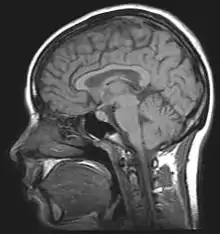

It is usually desirable to study memory in humans because we have the ability to subjectively describe experiences, and have the intellect to perform complex and indirect tests of memory. Lesion studies allow us to reduce the neural mechanisms of memory, and results from finely constructed psychological tests can help us make inferences about how memory works. Neuropsychologists attempt to show that specific behavioural deficits are associated with specific sites of brain damage. The famous case of HM, a man who had both his medial temporal lobes removed resulting in profound amnesia, illustrates how brain damage can tell us a lot about the inner workings of memory. One of the fundamental problems with studying human patients who have already acquired brain damage is the lack of experimental control.[1] Comparisons usually have to be made between individuals; exact lesion location and individual differences cannot be controlled for.

Cognitive neuroscience aims to reduce cognition to its neural basis using new technologies such as fMRI, repetitive transcranial magnetic stimulation (rTMS) and Magnetoencephalography (MEG) as well as older methods such as Positron emission tomography (PET) and Electroencephalography (EEG) studies. Due to the correlational designs used in fMRI, many scientists have coined this up and coming field as the new phrenology in the sense that techniques such as fMRI rely heavily on complex statistics.[17] Type 1 errors can lead scientists to draw premature and incorrect causal relationships if improper designs are used.[18]

A major complication that is raised in memory research is its fallible nature in humans. Having the ability to recall memories does not necessarily mean they are accurate. Our ability to store and process what is going on around us relies on memory being a constructive, fallible process. The technologies explained above may show areas of activation associated with certain behaviors, but without any idea of lesion location, it is difficult to pinpoint exactly what part of the brain relates to which behavioral deficits observed. Neuropsychologists have created various tasks designed to assess specific types of memory so that inferences about lesion location can be drawn from poor performances on these tests. Neuropsychological tests can aid us in understanding specific types of memory associated with specific sites of brain damage.

The neurotoxic lesion technique has proven to be essential for studying the neural basis of behavior and memory in animals. Neurotoxins can be used to selectively damage very specific nerve tracts in the brain.[30][31][32] Pertaining to the study of memory, areas of interest include the hippocampus, the rhinal cortex, the pre-frontal cortex, and the frontal cortex. The neurotoxic lesion technique uses neurotoxins such as ibotenic acid to selectively disrupt or kill specific neural tracts in any of the areas described above. The animal is anaesthetized and immobilized so that stereotaxic instruments can be used to drill holes in specific locations of the skull. Scientists can then carefully administer microinjections of neurotoxins to damage only the neurons in specific brain areas. This technique allows for the selective lesioning of areas of interest and leaves surrounding supportive tissue unaffected.[30][31][32]